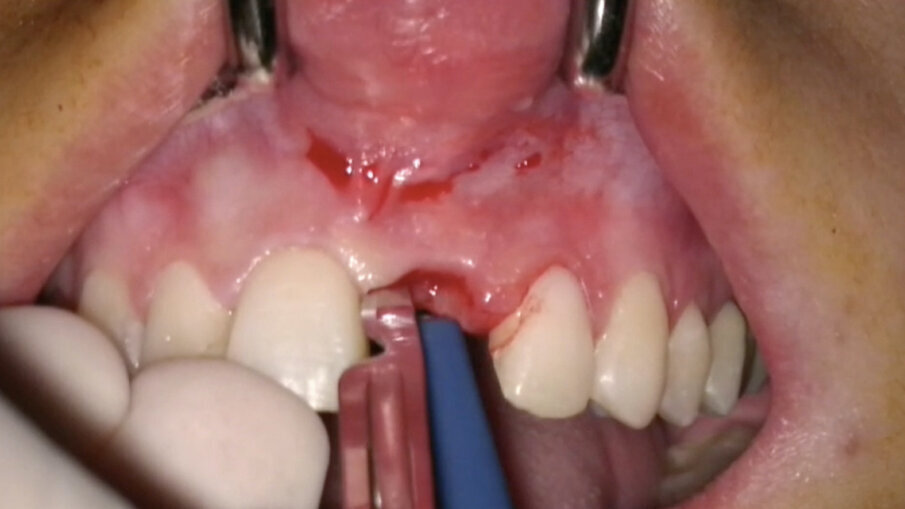

Non vanno eseguite incisioni di scarico in quanto non sono necessarie (Fig. 13). Diversamente, nei casi di edentulia parziale frontale deve essere eseguita un’incisione vestibolare (Fig. 14) a partenza intra-sulculare dai denti adiacenti. Come noto, tale incisione non deve coinvolgere la parte coronale delle papille: l’interessamento dei picchi ossei, infatti, porterebbe inevitabilmente alla perdita di 1-1,5 mm di osso con compromissione dell’estetica finale. In entrambi i casi, al fine di posizionare una matrice in collagene, verrà eseguita un’incisione a spessore parziale creando una piccola tasca mucosa corrispondente alla porzione buccale della zona trattata (Fig. 15).

- Posizionamento della matrice e sutura

La matrice va posizionata nella tasca mucosa creata in precedenza (Fig. 22). Nel caso in cui siano state eseguite incisioni, i tessuti molli devono essere ermeticamente suturati sopra di essa, mentre, nel caso opposto, deve essere delicatamente inserita in modo tale da sommergerla completamente.

Fig. 15_Incisione verticale per la creazione della tasca mucosa a spessore parziale.

Fig. 22_Posizionamento della matrice in collagene.